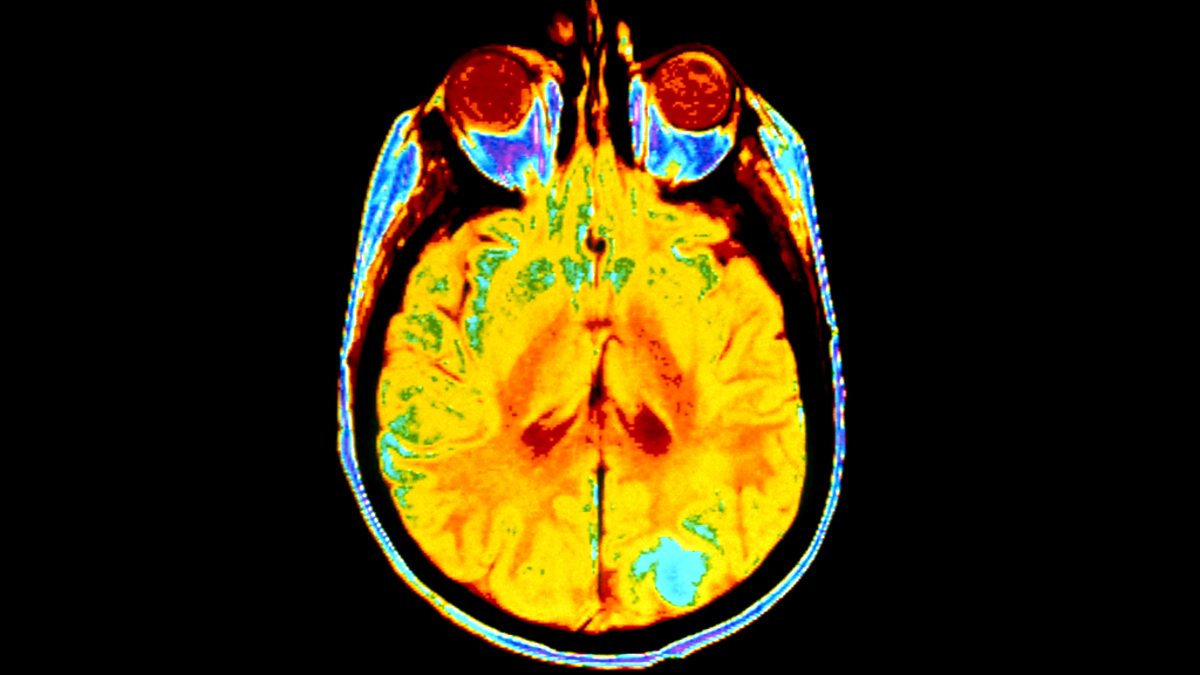

Ben Silburn journeys around our brain's neural network to discover how it creates and stores memories.